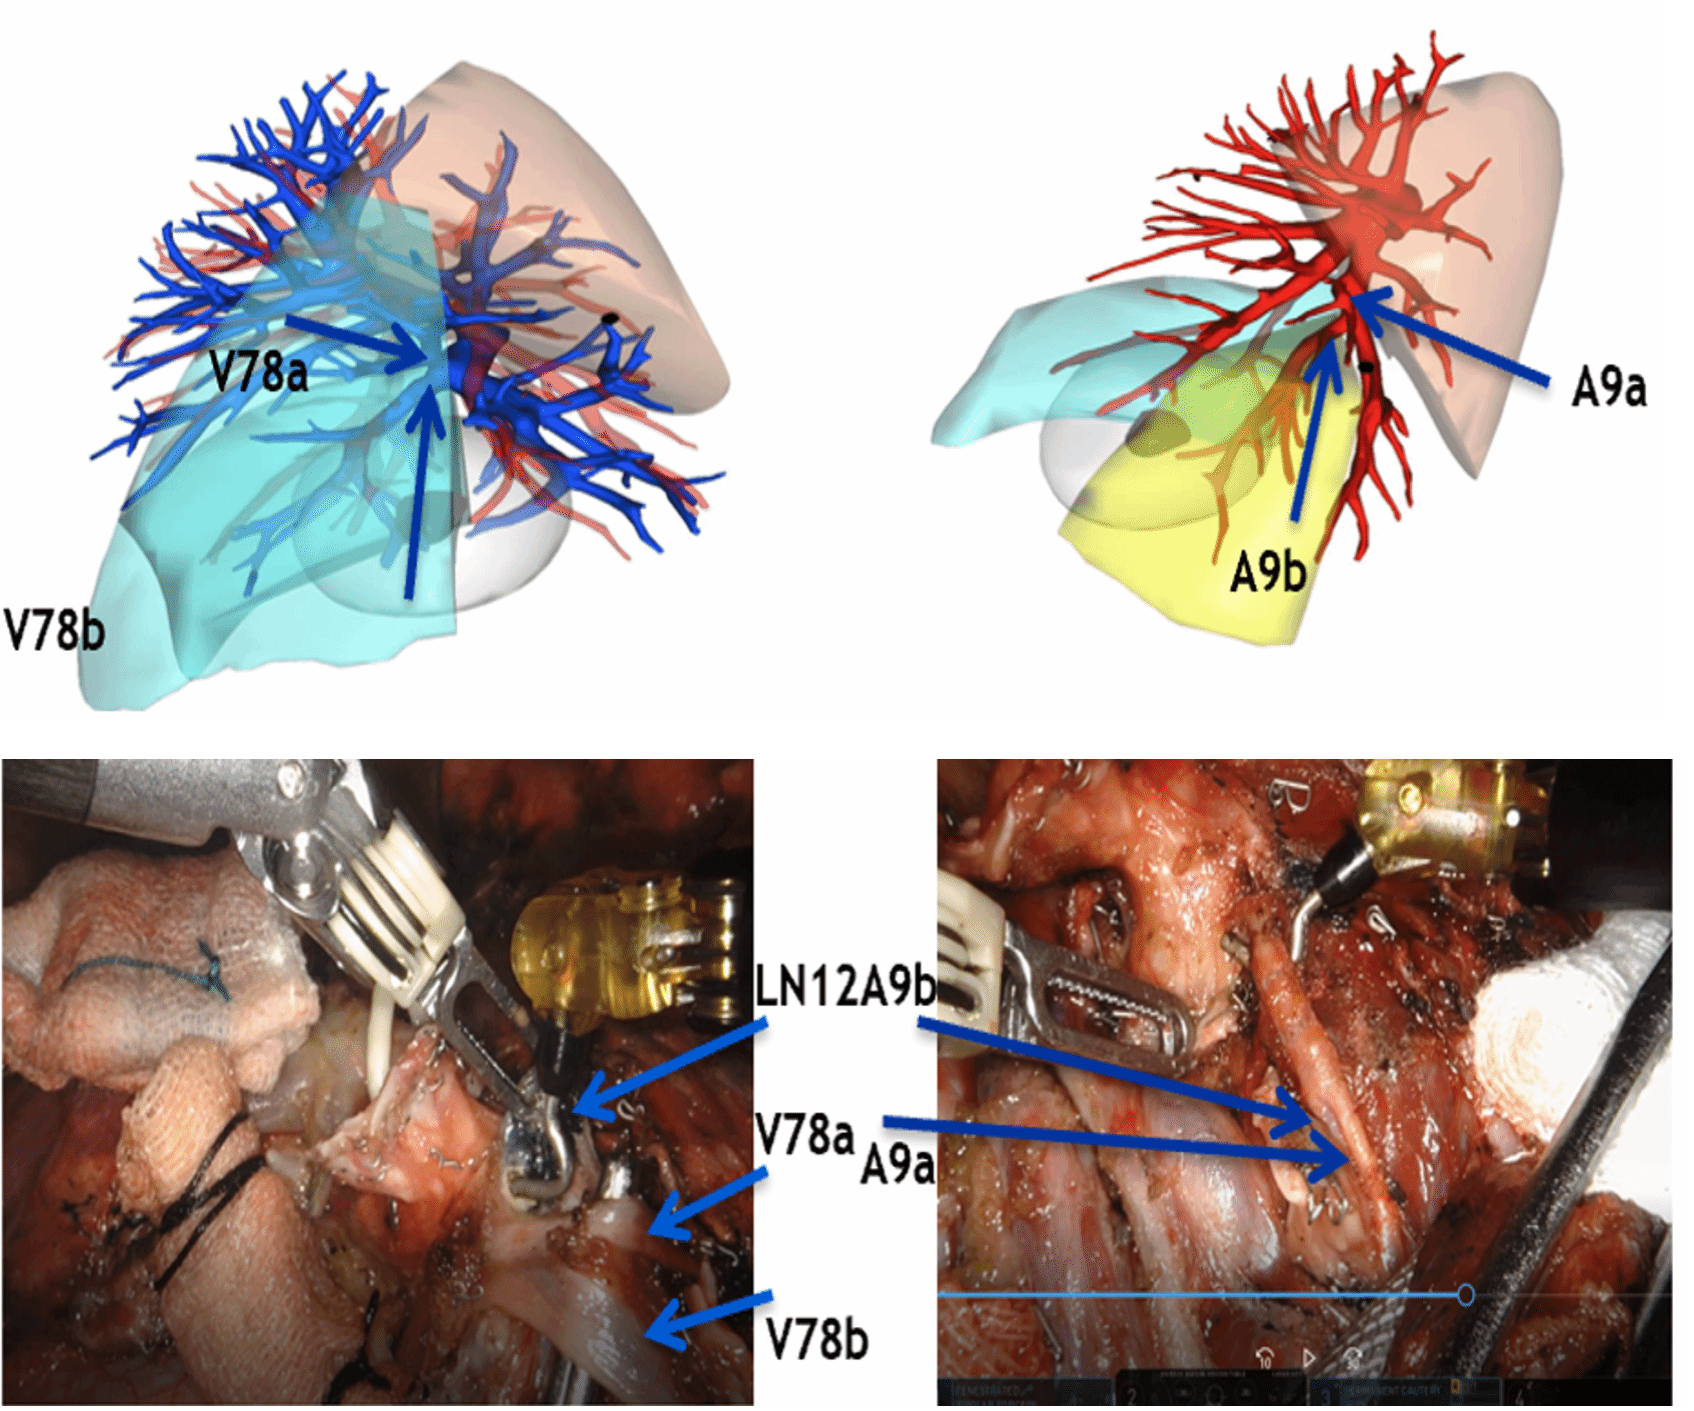

常规腔镜方面,以胸部肿瘤外科为主,开展肺叶、肺段、复合肺段/亚段切除、解剖性肺切除、袖状切除等手术,包括单孔到多孔等各种入路。在北京市较早开展微创食管癌切除,积累了丰富的经验。纵隔肿瘤方面,开展包括剑突下及其他入路胸腺切除、胸腺扩大切除,无名静脉成型等。同时结合锚丝定位、术前三维重建技术和荧光腔镜技术使手术安全高效。